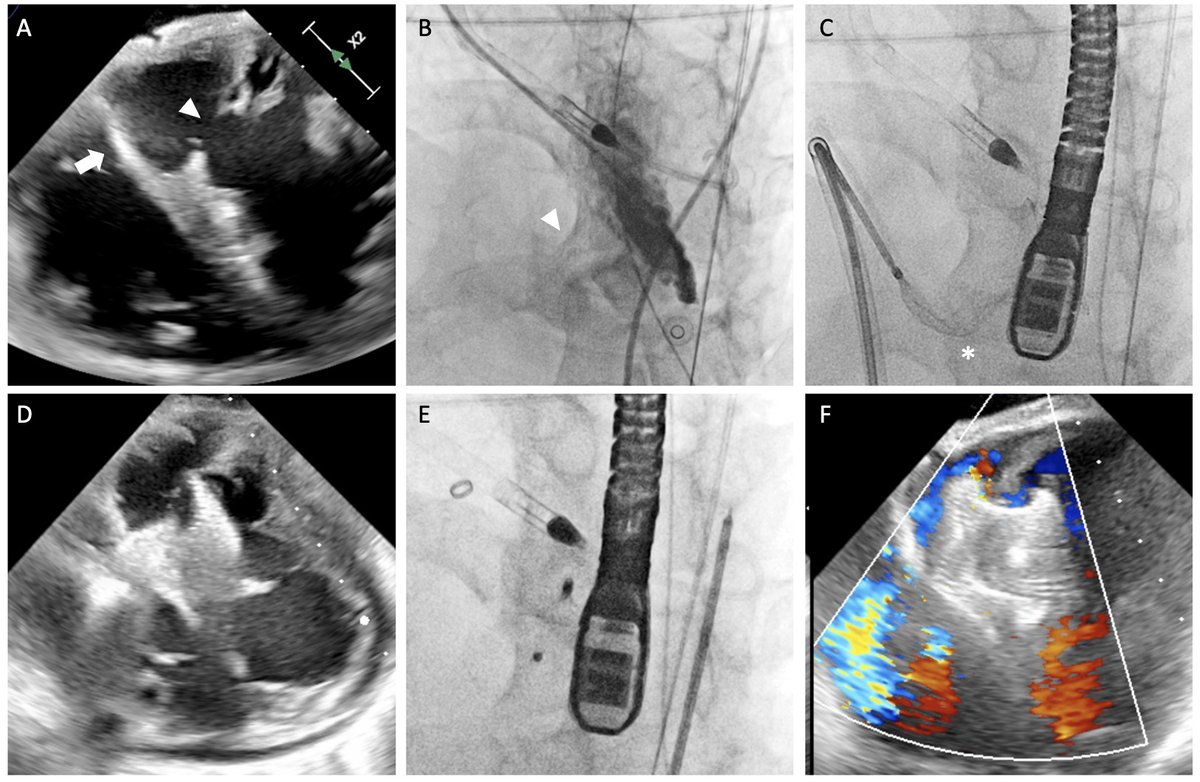

Just published in JACC Intervention! (Possibly First-in-Asia) Transcaval Impella-Assisted CHIP-PCI and Transcaval TAVR, featuring removal of Impella in freshly deployed TAVR https://t.co/L6d149reZ8…

@JACCJournals @MDT_StructHeart @TCTMD @ACCinTouch @jjmt_heartrecov #impella